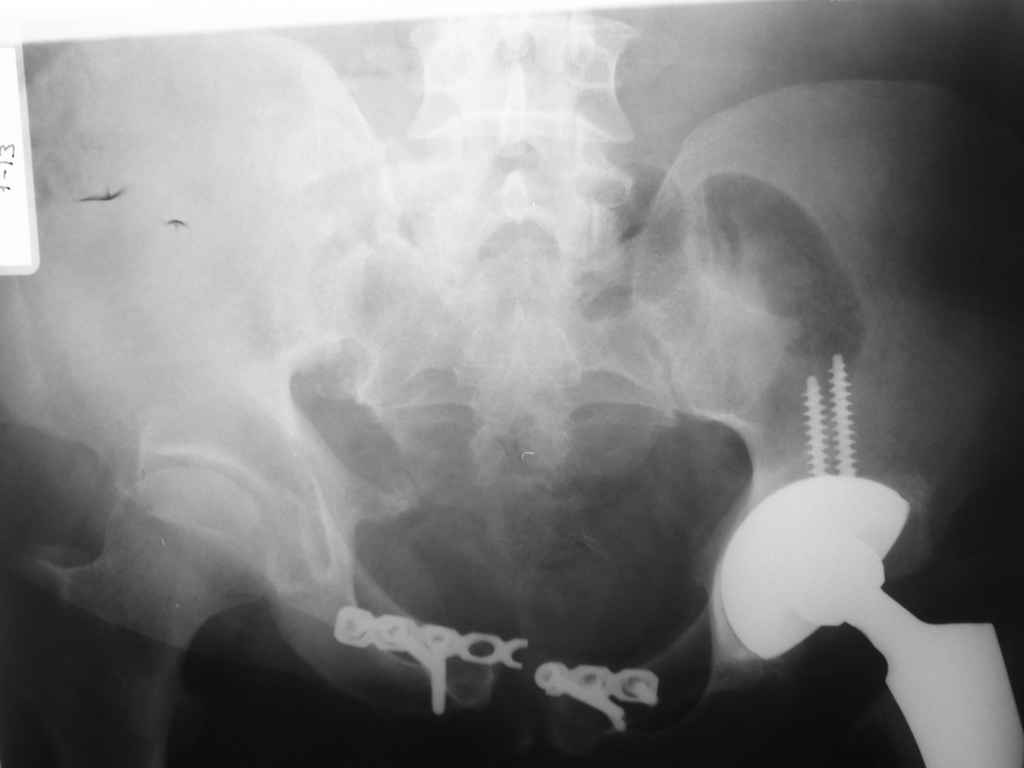

Добрый день ув.коллеги. С прошедшими вас праздниками. Представляю вашему

вниманию пациента с застарелой травмой таза. Анамнез: тяжелая сочетанная

травма в 2001г.(старых снимков нет) Таз прооперировали следующим

образом: стержневой аппарат(передняя рама)+ пластину на лонное

сочленение. В связи с тотальным парастержневым воспалением с которым

боролись3нед. аппарат демонтирован. В 2002 операция в плановом порядке:

тотальное замещение левого ТБС. в 2003г. диагностирована фрактура

пластины, в связи с чем выполнен повторный накостный остеосинтез лонного

сочленения. В течении последующих 3-х лет пациент не обращался.

Обратился в декабре 2007 с связи с выраженными болями в Области правого

КПС,лонного сочленения. Повторных травм не было. Снимок прилагается

(извините за качество),если нужны будут другие проекции вышлю. Пациент

передвигается только с помощью костылей. Длина конечностей

слева(+2см).Помогите определиться тактически в какой очередности и каком

объеме выполнять опер.вмешательство.